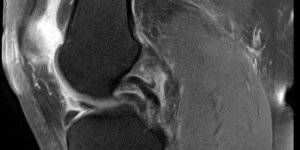

Knee – Bucket Handle Tear & ACL Tear

Case History 32 Year old female Felt a pop in the knee when doing box jumps. Developed knee pain with slow swelling. Improved a couple of weeks later. 5 Months later while doing weighted lunges, knee popped again. Improved again but residual pain persisted. Continued to do cross fit. Referred to MSK Physio by GP. Examination Mild end range flexion [...] Read more